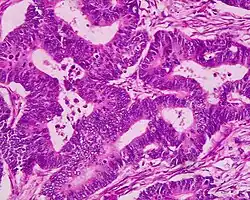

| Colorectal adenocarcinoma | 100% |

|

| |

Micrograph of a tubular adenoma – dysplastic epithelium (dark purple) on left of image; normal epithelium (blue) on right. H&E stain. -